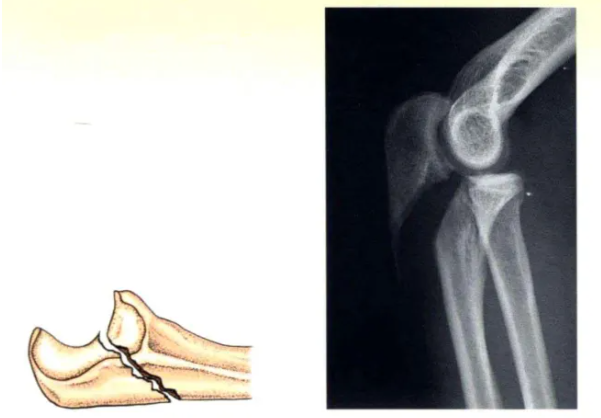

C型:斜(xie)形骨折(zhe)

C型:由(you)拉力(li)螺釘產生骨(gu)折間加(jia)壓(ya),并(bing)由(you)接骨(gu)板或張力(li)帶提供(gong)保(bao)護(“中和”)